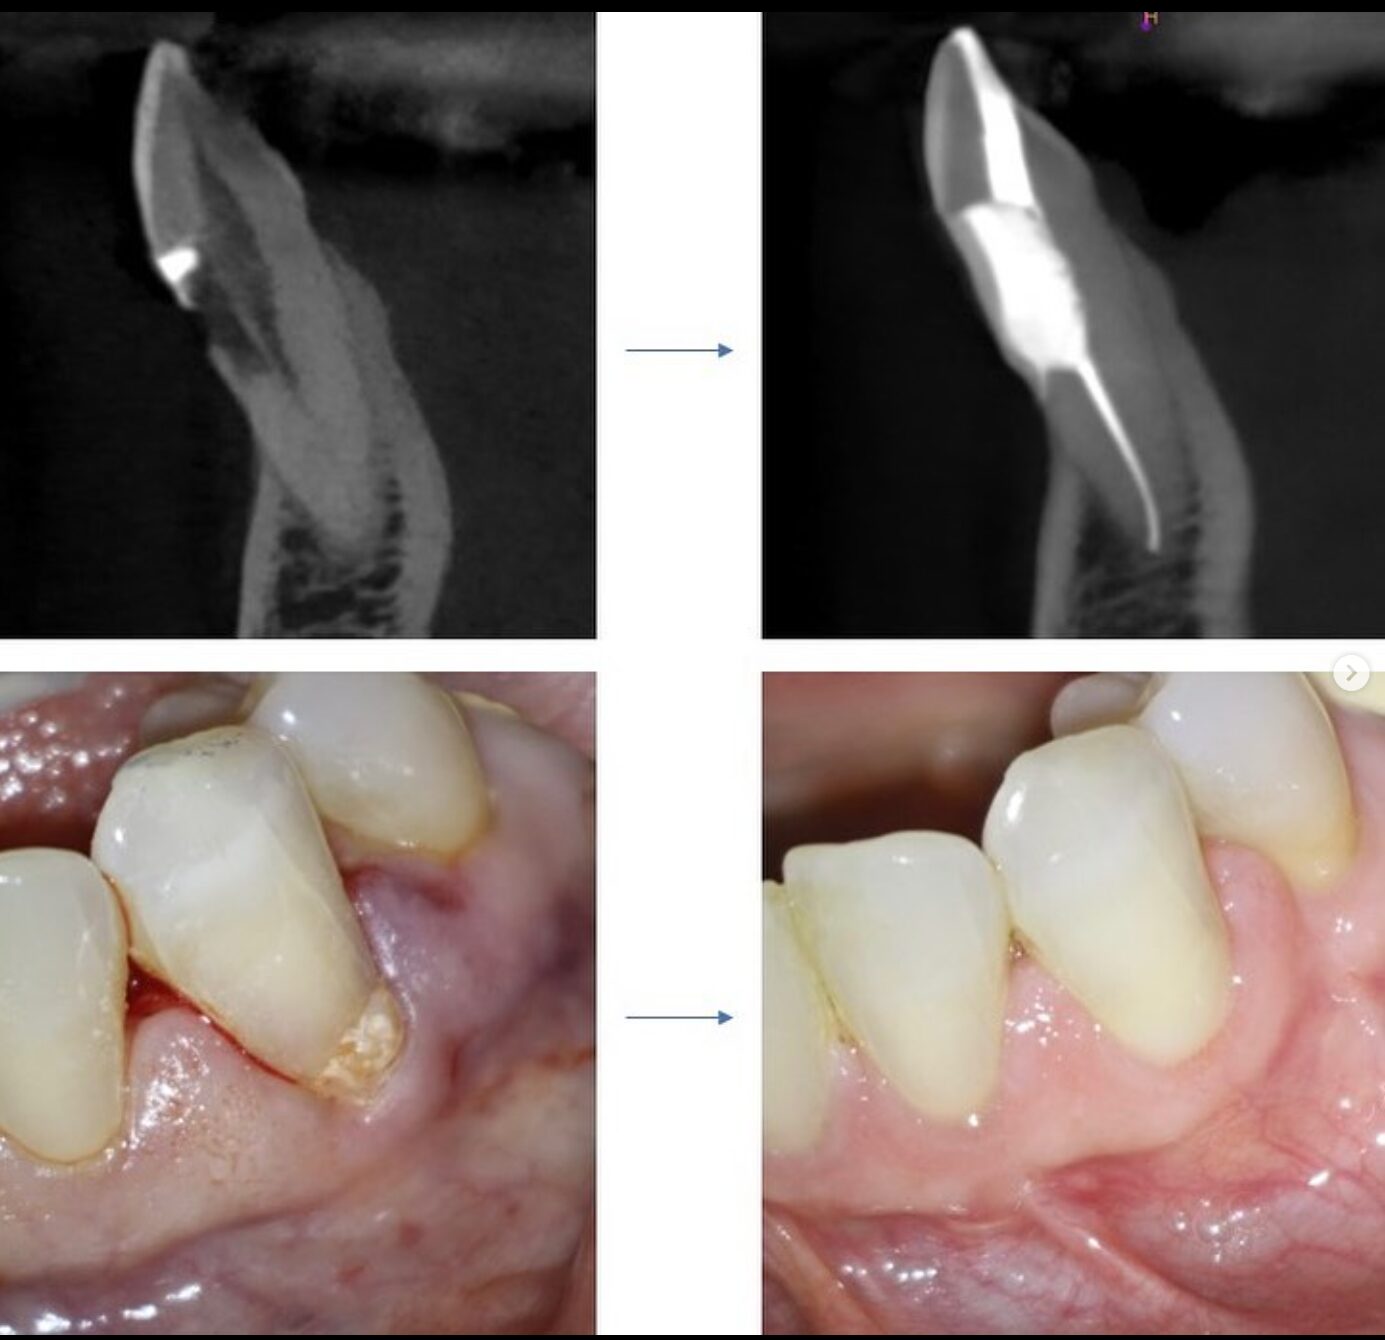

Case Studies

Discover all our case studies on Instagram by following @dana_point_endodontics and exploring our highlights or posts for in-depth insights and success stories!